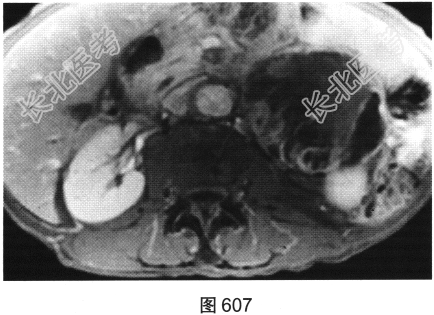

- [材料题] 患者女性,85岁,腹主动脉瘤破裂手术修复后,腹部疼痛。患者行腹部CT检查,见图603~图607。

- 简答题1、请对该病变CT影像表现进行描述。